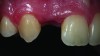

Fig 1. 45-year-old female with esthetically unpleasant direct composite veneer on tooth No. 8.

Figure 1